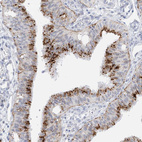

Immunohistochemical staining of human fallopian tube shows strong granular cytoplasmic positivity in glandular cells.